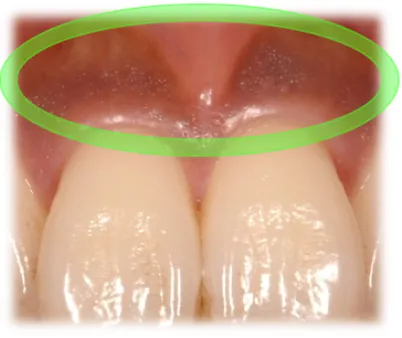

原因は歯周病です。被せ物を外すと中に歯周病菌がたくさん付着しています。

歯ブラシができない形態の被せ物だったので、汚れが溜まり歯茎に炎症を起こし、歯周病になり、黒く変色していました。 -

●歯茎の薄く凹んでる所は、汚れが溜まりやすく歯周病を再発しやすいので歯茎の移植を行い、本来の厚みにする。

●徹底的な歯周病治療を行い、健康的な歯茎にする

●歯ブラシがきちんと行えるような被せ物の形態にする

歯ブラシがきちんと行えるような被せ物の形態にしたことで、再び歯周病を発症することを予防し、今回の処置によって綺麗になった歯茎をより長く健康的に維持し続けられるように治療を行いました。 当院では、 その場しのぎではなく長期的に患者様のご希望を満たせるような治療を心がけております。